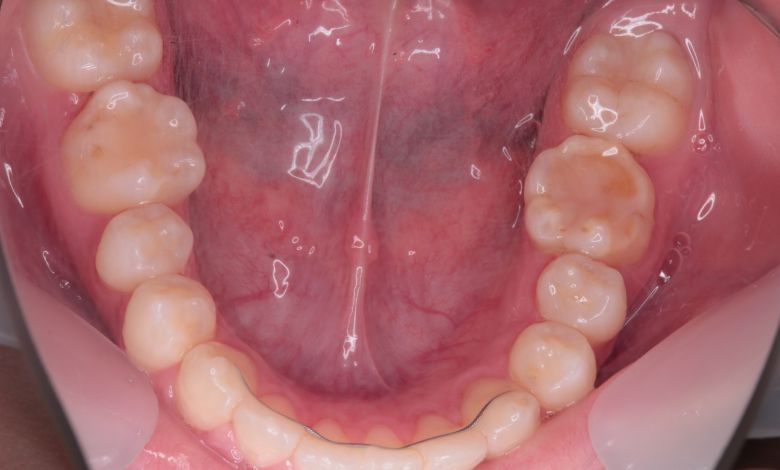

他院にて上下左右4本の抜歯を前提とした矯正治療を提案されていました。上顎・下顎ともに歯列弓が狭く、

V字型の弓状を呈していたため、叢生(歯の重なり)が強く、噛み合わせにも不調和が見られる状態でした。

上顎歯列はV字型に近く、全体的にアーチが狭窄している状態

叢生が解消され、歯列全体にわたり滑らかで調和のとれた配列が得られています

上下の咬合関係も不正で、機能的にも審美的にも問題のある状態でした

上下の前歯の重なりが解消され、歯軸の傾きも整いました。咬合関係も安定しています

下顎の歯列では、前歯部に強い重なりが見られ、中切歯および側切歯がねじれたり前後にずれて生えているのが確認できる

術前に認められた前歯3本の強い重なりは完全に解消され、スムーズな歯列が形成されました。

精密検査の結果、抜歯を行わずに歯列弓を拡大する治療方針を選択。歯が正しい位置に並ぶスペースを

確保したことで、歯列は自然なU字型に整い、叢生が解消されました。見た目の改善だけでなく、

咀嚼機能の向上や清掃性の改善といった機能面での効果も期待できます。